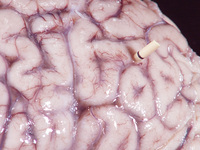

Autópsia macroscópica do cérebro de paciente com meningite criptocócica exibindo a superfície com um aspecto "vidrado". Também há um shunt (derivação) presente

Do acervo pessoal de Robert E. Schmidt; usado com permissão